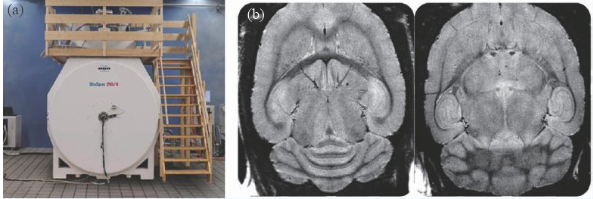

除了人體成像的超高場磁共振成像裝置外,用于動物臨床前應用的裝置在磁場強度上遠遠走在了前面,10 年前就出現(xiàn)了16.4 T/26 cm動物成像MRI 機,德國的Bruker公司在幾年前也推出了更高磁場的動物成像機—— 21 T/11 cm動物成像MRI機(圖8)。

圖8 (a)21 T MRI磁體;(b)大鼠的腦部高分辨率成像(分辨率26 μm)